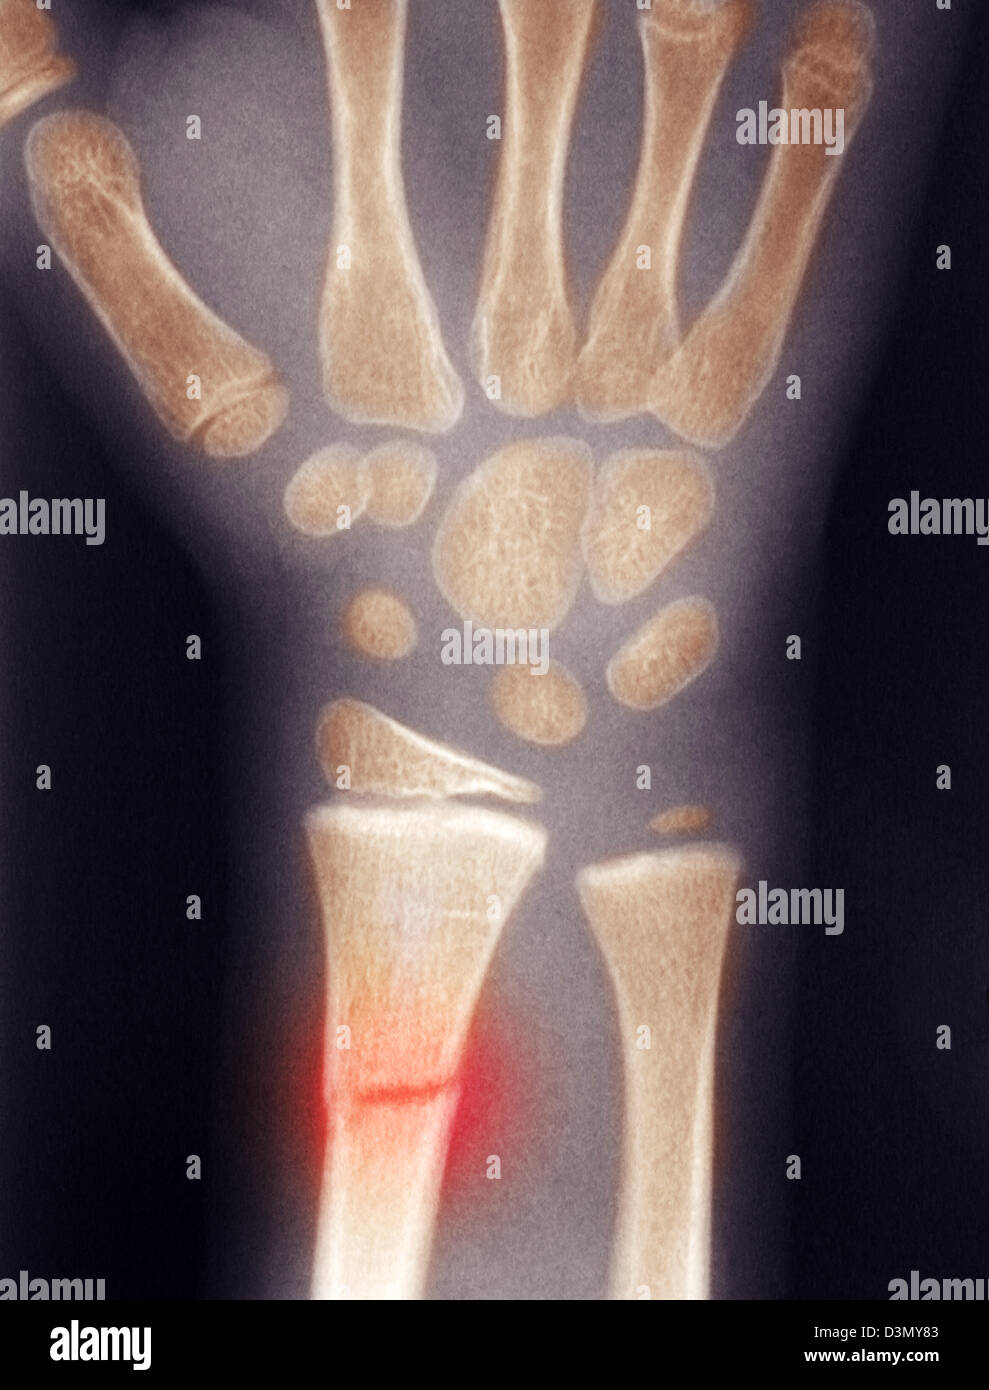

Fissure Fracture X Ray . 'toddler's fracture' = tibial spiral fracture in a toddler. It is necessary when studying the x. Stress fractures of the tibia result from repeated low force trauma. When a person has a bone fracture, one of the first things a person will want to know is how bad it is. Proper description of fractures with knowledge of injury mechanisms, consequent care and complications. It provides an exit route for the chorda tympani from the middle ear to. Transverse, oblique and spiral fractures. The petrotympanic fissure (glaserian fissure) can be visualized on axial and sagittal images (figs. A fissure fracture is noted at the middle third of the right metatarsal bone, more clear on the oblique view (yellow arrow). To determine the severity and treatment/recovery time, doctors will typically perform an. Tibial fractures usually result from high force trauma. Importance of standard radiography of the wrist.

Plain x ray showing a recent fissure fracture at the lower part of a Fissure Fracture X Ray Stress fractures of the tibia result from repeated low force trauma. To determine the severity and treatment/recovery time, doctors will typically perform an. 'toddler's fracture' = tibial spiral fracture in a toddler. It provides an exit route for the chorda tympani from the middle ear to. Tibial fractures usually result from high force trauma. It is necessary when studying the. Fissure Fracture X Ray.